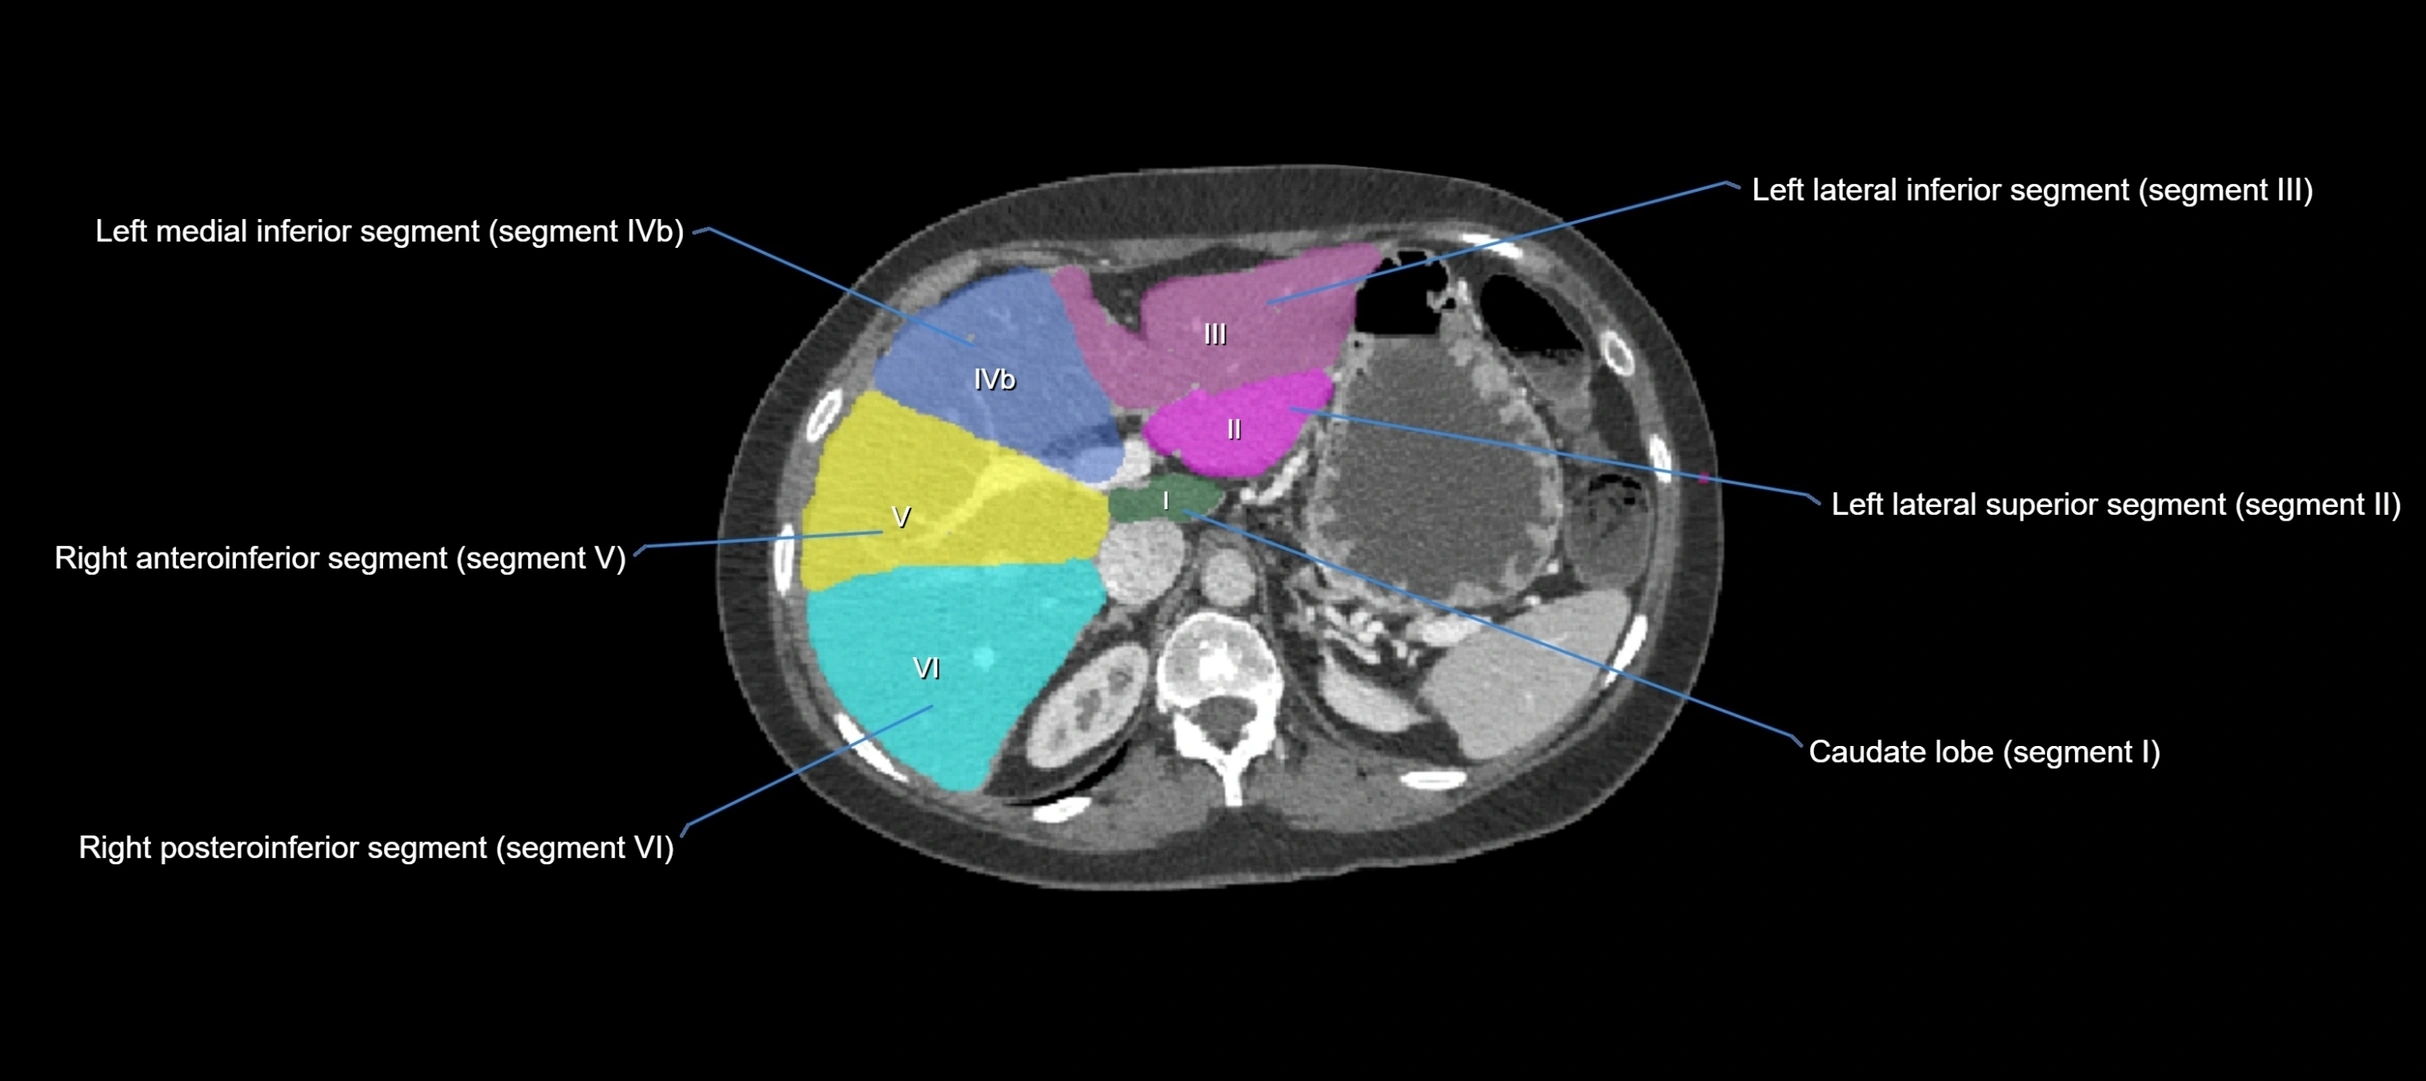

CT Image

image